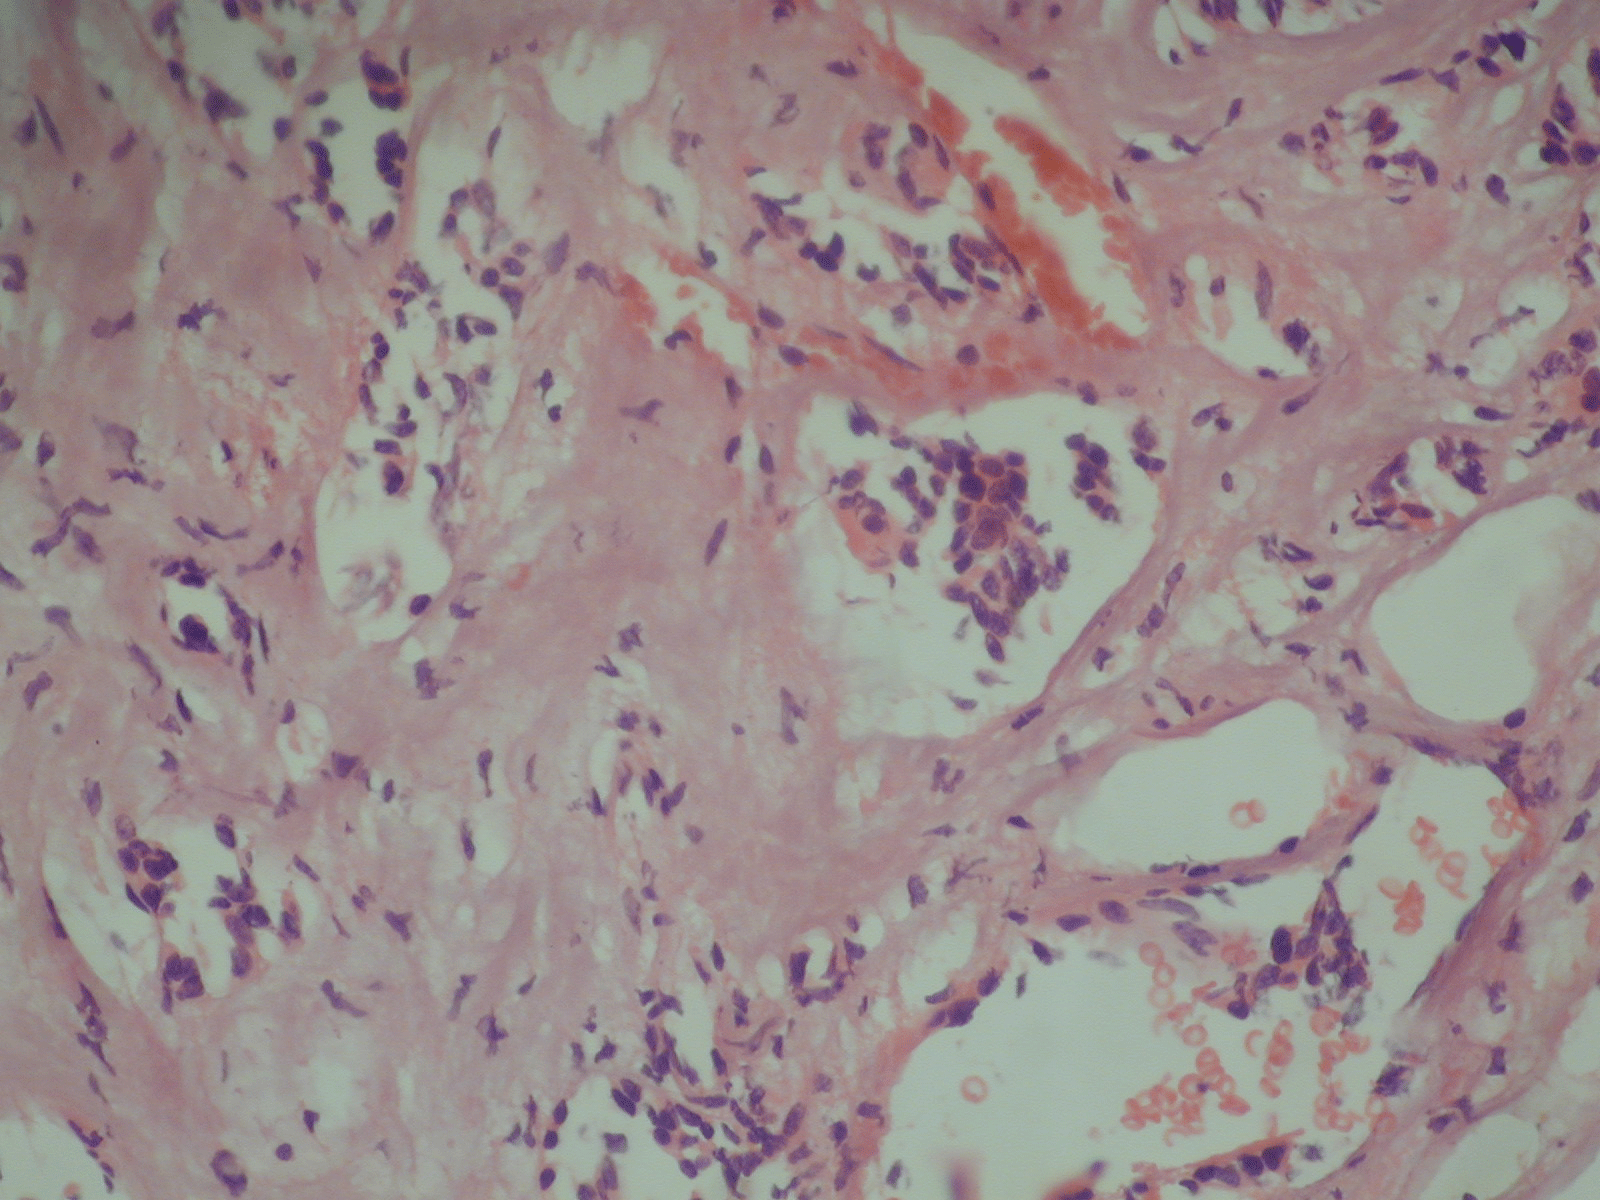

The histological picture of the recurrent pituitary adenoma.